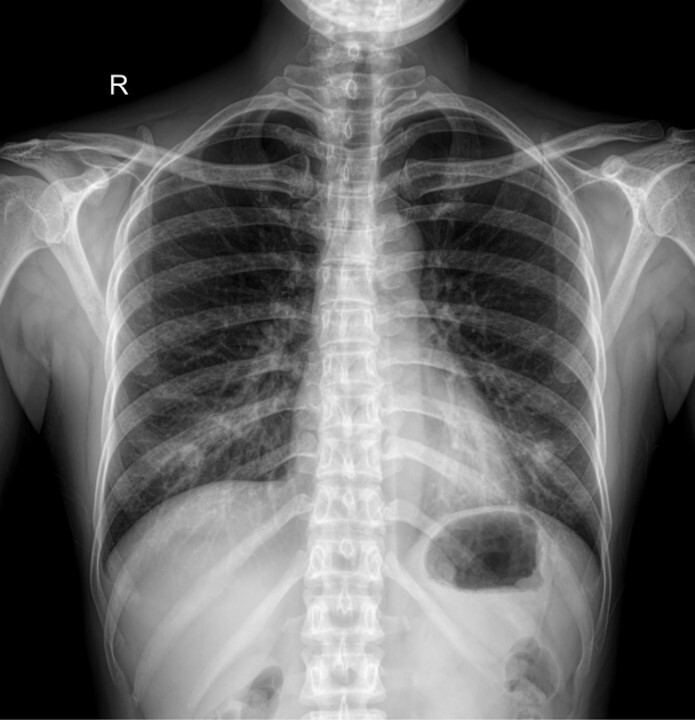

Q

x ray

A

-is this a nodule or a nipple shadow

-right lower